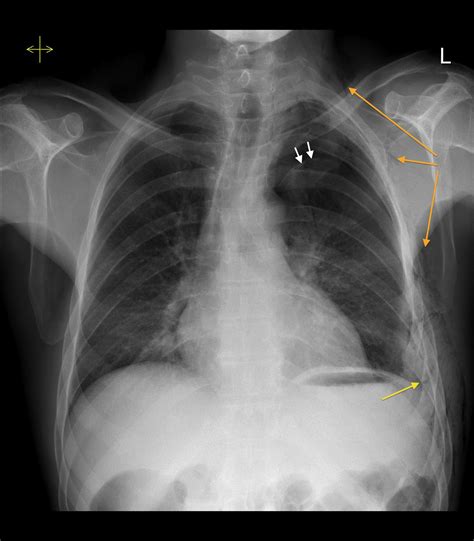

Rib fractures